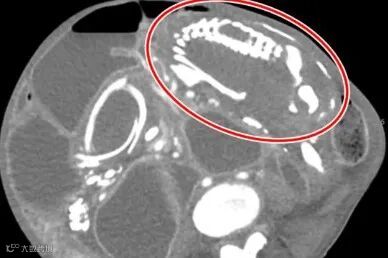

一孕婦腹痛延遲就醫30年 74歲終產下「石胎」

近日台北醫學大學分享「石胎症」病例,一名74歲婦女因腹痛就醫,竟發現腹部有一個「30年前的胎兒」已鈣化成「石胎」,最後醫療團隊將胎兒取出,其已成冷冰冰的石塊。

在醫療落後地區,孕婦可能因無法及時診斷異位妊娠,導致胎兒在體內停留多年。這聽起來像電影情節,但確實是極少見的醫療案例,常見情形是子宮外孕(胚胎在子宮外著床)的胚胎死亡,因體積過大無法被細胞吞噬,人體為防止感染,會以鈣質將其「封存」。

據統計,患有「石胎」的女性平均診斷出的年齡為55歲,最大的100歲,「石胎」的平均攜帶時間22年,醫學史上僅記錄約300例。